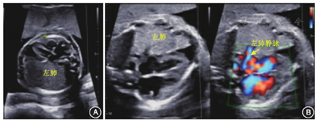

本次超声检查:胎儿双顶径60.3 mm,头围224.6 mm,腹围184.5 mm,股骨长40.4 mm,肱骨长38.5 mm,羊水指数115 mm,胎心率155次/min,胎盘厚度22 mm。胎儿左肺面积8.4 cm2;右肺显示不清,未见肺动脉分叉,未见肺静脉进入左心房;心脏右移,心尖部见深约3.8 mm液性暗区。考虑右肺缺如或发育不全,左肺增大,心脏右移;余未见明显异常(图1)。检查后,产前诊断中心进一步提供咨询意见:(1)行羊水染色体核型+染色体微阵列分析(chromosomal microarray analysis, CMA)检查,排除相关遗传性疾病;(2)行胎儿MRI检查;(3)新生儿外科专家咨询,了解相关风险及预后;(4)超声监测胎儿生长发育情况(孕26~28周复诊),观察有无合并其他结构发育异常、左肺发育情况,以及有无胎儿水肿、胸腔积液,纵隔移位等。孕妇及家属选择行介入性产前诊断,遂于孕24周行羊膜腔穿刺术。羊水染色体核型示G显带320条带水平未见数目异常和明显结构异常;CMA为arr[hg19] (1-22)×2,(XN)×1,未见明显异常。新生儿外科专家会诊后建议尽早行胎儿MRI检查,进一步了解胎儿肺部发育情况,并告知一侧肺发育不全的相关风险。孕妇及家属选择继续妊娠,但未行MRI和胎儿超声心动图等检查。

注:L:左侧(left);R:右侧(right)